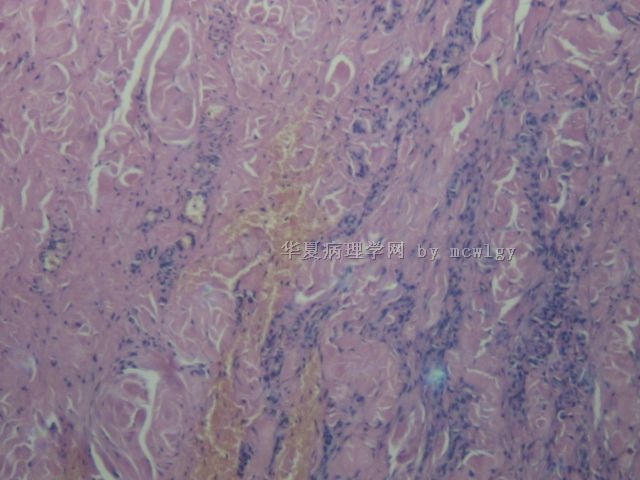

姓    名: ××× 性别:  男 年龄:  42

简要病史:  发现无痛肿物10天。

肉眼检查:  不整形3.5*3.5*2.5CM,红褐色,切面灰黄红褐色,质中.

结节性筋膜炎。

结节性筋膜炎

结节性筋膜炎又称假肉瘤性筋膜炎,发病原因不明,可能与外伤 或感染有关。该病有两个最重要的临床表现:一是迅速生长的肿块,通常在12周出现小肿块结节,病变处伴有疼痛、麻木或感觉异常;二是肿块通常较小,一般不超过2厘米,且病变有自限性。 本病易误诊为恶性纤维组织细胞瘤、纤维肉瘤、黏液性脂肪肉瘤等。美国有资料表明,结节性筋膜炎误诊率高达50%,过度诊断为恶

性的达20%。由于结节性筋膜炎是一种非肿瘤性病变,临床治疗主要

为局限手术切除,复发率低

再传几张图片。能否考虑滑膜瘤?

结节性筋膜炎不典型,可以描述性诊断,其内见滑膜细胞增生伴出血,好像还有些异物之类的东西